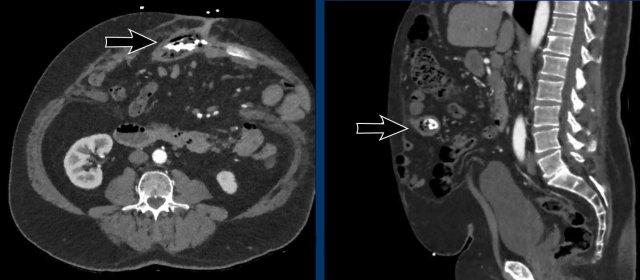

Ở một bệnh nhân khác, Tỷ lệ Cơ thẳng bụng trên Khuyết tật là: (73 mm + 81 mm) / 51 mm = 3.

Trái ngược với trường hợp trước, việc đóng thoát vị có thể thực hiện được mà không cần tiến hành kỹ thuật tách thành phần.